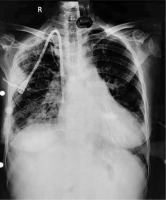

A 51-year-old chronic kidney disease patient with chronic obstructive pulmonary disease underwent catheter insertion with a Hemosplit 14.5 Fr haemodialysis catheter (Bard Access Systems, Utah, USA) through the right subclavian vein in the nephrology unit of our institute. The procedure was conducted with good flow through one port and poor flow through the other port. The catheter guidewire was removed completely but was seen to be coiled on extraction. Some amount of force was also required during the insertion of the catheter as reported by the operator. A post-procedural chest X-ray showed normal position of the catheter. Anticipating that the poor flow through one port could be due to abutment of the catheter against the vessel wall or due to a clot and because of the normal X-ray (Figure 1), the patient was taken for haemodialysis. Two hours into dialysis, the patient became hypotensive with a systolic blood pressure of 70 mm Hg. Dialysis was immediately terminated and imaging in the form of non-contrast neck and chest computed tomography (CT) in view of the patient’s renal status was done. It showed the catheter entering through the right supraclavicular region traversing posterior to the medial end of the clavicle, right subclavian vein, superior vena cava and traversing in the right part of the middle mediastinum. The catheter was seen in close contact with the right pulmonary artery and left atrium with air foci adjacent to the catheter in the left atrium (Figures 2 A, B). As attempts at haemodynamic stabilisation did not succeed, the patient was taken immediately into the operation theatre for exploration by the cardiovascular and thoracic surgery department.